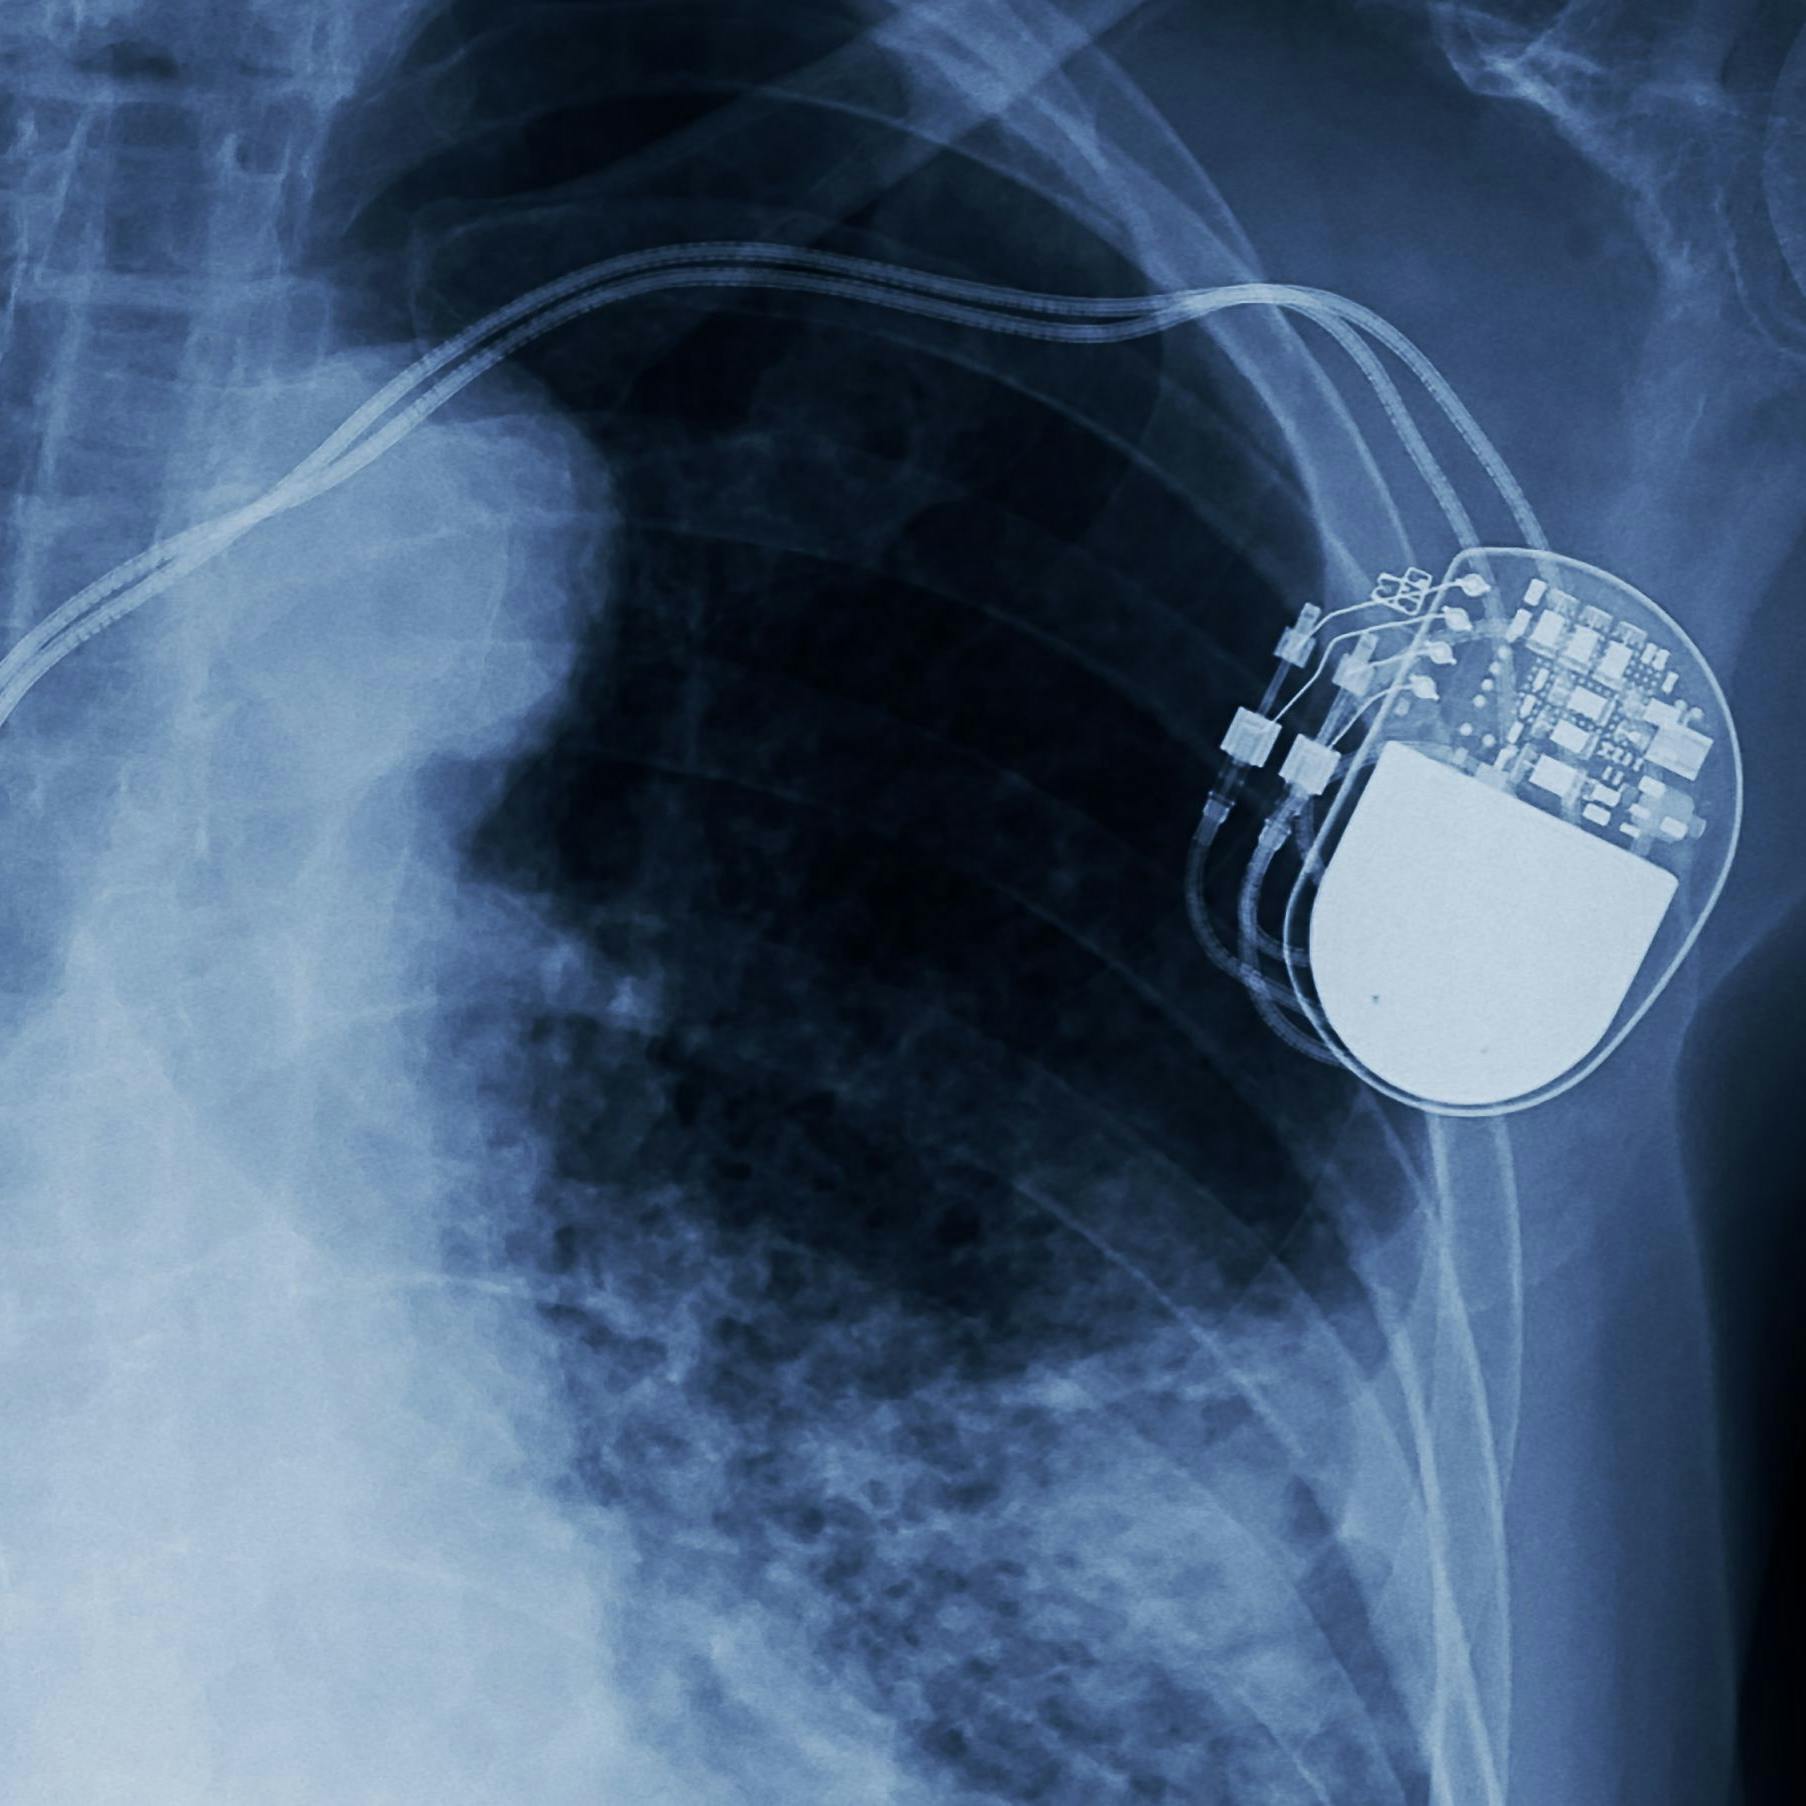

Eine Woche nach seinem Herzstillstand im Gruppenspiel gegen Finnland und den geglückten Wiederbelebungsversuchen auf dem Rasen wurde Eriksen operiert, er bekam einen Defibrillator eingesetzt. Bis heute fehlt eine genaue Diagnose, Experten gehen jedoch davon aus, dass es eine nicht heilbare Herzerkrankung gewesen sein muss. Wahrscheinlich eine genetisch bedingte Myokarditis, eine Herzmuskelentzündung, die selbst dann lange unentdeckt bleiben kann, wenn man Profisportler ist, also regelmäßig durchgecheckt wird.

Die Frage, ob Christian Eriksen jemals wieder professionell Fußball spielen wird, könnte schon bald beantwortet werden. Gerüchten zufolge könnte Ajax Amsterdam an einem Spielertausch mit Inter Mailand interessiert sein. Im Gegensatz zur niederländischen Eredivisie verbietet die italienische Serie A den Einsatz von Spielern, die einen Defibrillator unter der Haut tragen. So wie Amsterdams Daley Blind. So wie Daniel Engelbrecht vom damaligen Drittligisten Stuttgarter Kickers, der 2014 – Herzmuskelentzündung, chronische Herzrhythmusstörungen – nach vier Operationen noch einmal zurückkehrte auf den Platz, als erster Spieler in Deutschland. Die Probleme blieben, drei Jahre später gab Engelbrecht den Fußball auf.